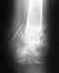

23.04.2012 мне провели открытый остиосинтез левой большебердцовой кости аппаратом внешней фиксации т.е.ап. илизарова.

сказали ходить с ним 2 месяца(до 6 июля) но у меня недавно начались боли в ноге, она сильно опухла и началась подниматься высокая температура.че мне делать, подскажите,может возможно снять аппарат раньше на неделю?